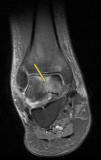

Clinical CaseA 41 year old male with no medical history of interest, presented at the surgery with right knee pain and minimum trauma. Diffuse bone marrow oedema involving the external condyle was reported. Four months later he presented with bone marrow oedema in the ipsilateral internal condyle (Fig. 1). In other magnetic resonance images we found new bone marrow oedema extension, in the internal femoral condyle of the contraleteral knee and later in the external condyle and pain in the right knee, the NMI of which also showed bone marrow oedema (Figs. 2 and 3). Treatment with NSAIDS was administered and partial load-bearing but this was ineffective.